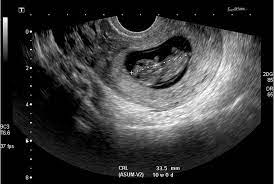

Recordemos que en esta semana el embrión tiene cuatro semanas de edad ya que habitualmente al contabilizar las semanas de embarazo se empieza desde la. Aproximadamente 6 semanas más o menos en el embarazo los latidos del corazón del feto se pueden detectar a través de un ultrasonido que sin embargo puede variar mucho en situaciones reales.

No escuchar el latido del feto a las 6 semanas es normal y no hay razón para preocuparse. Aproximadamente 6 semanas más o menos en el embarazo los latidos del corazón del feto se pueden detectar a través de un ultrasonido que sin embargo puede variar mucho en situaciones reales. El corazón de un feto late muy rápido no debes asustarte cuando te realizen la ecografía y escuches un latido a 150 pulsaciones porque es normal. La actividad cardiaca no se inicia antes de los 28 días de embarazo porque durante las cuatro primeras semanas tras la fecundación tu futuro bebé tiene muchas cosas que hacer. Cuando no es posible ver el embrión yo escuchar sus latidos cardiacos la mujer tendrá que repetirse la ecografía de ultrasonido pasadas una o dos semanas para descartar la posibilidad de que se trate de un embarazo anembrionado. Los médicos generalmente no recomiendan un ultrasonido a las 6 semanas ya que generalmente no muestra nada o muy poca imagen del feto incluso para un embarazo. Fue la mejor noticia que nos dieron a mi y a mi novio y estamos ilusionados pero ahora estamos y especialmente yo estoy muy tristeee porque estoy de 8 semanas y el latido del corazon de mi bebe no se escucha.